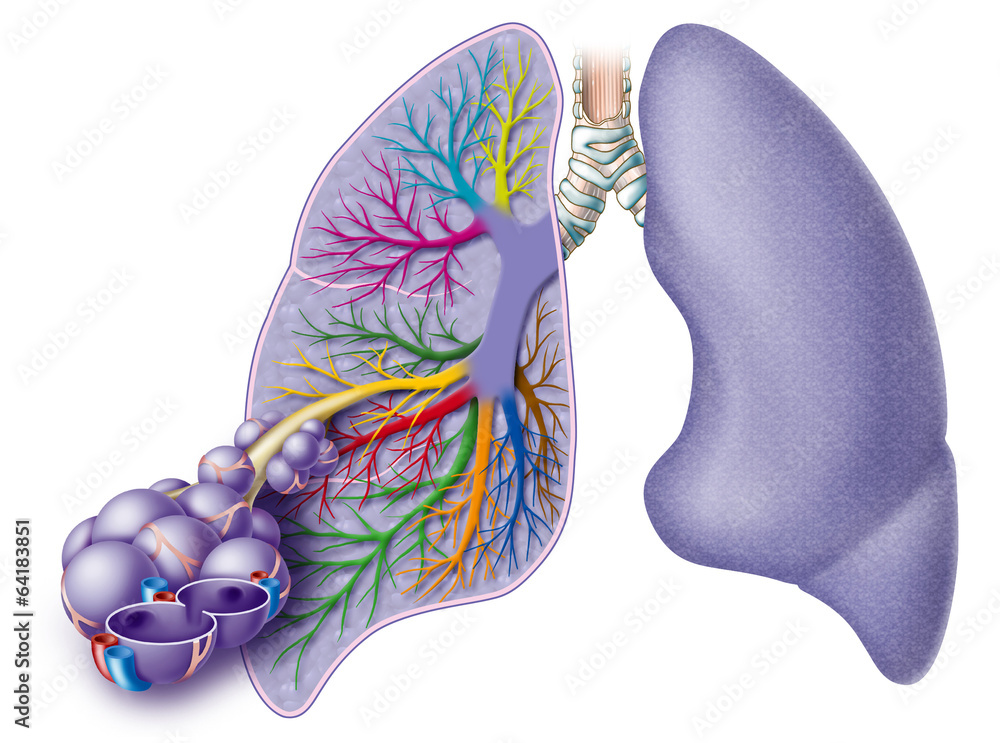

Пороки бронхолегочной системы

Пороки бронхолегочной системы 116 фото